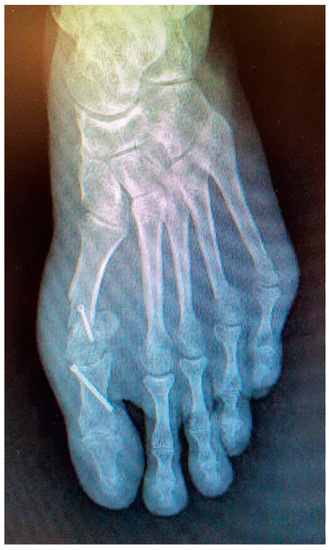

Radiographic examination after one year following the second surgery showed signs of severe joint destruction compatible with MPJ resection arthroplasty with significant shortening of the first toe (Figure 5). The patient was treated conservatively with orthopaedic insoles.

Figure 5. Postoperative radiography one year after the second procedure. Signs of severe joint destruction compatible with resection arthroplasty can be observed.